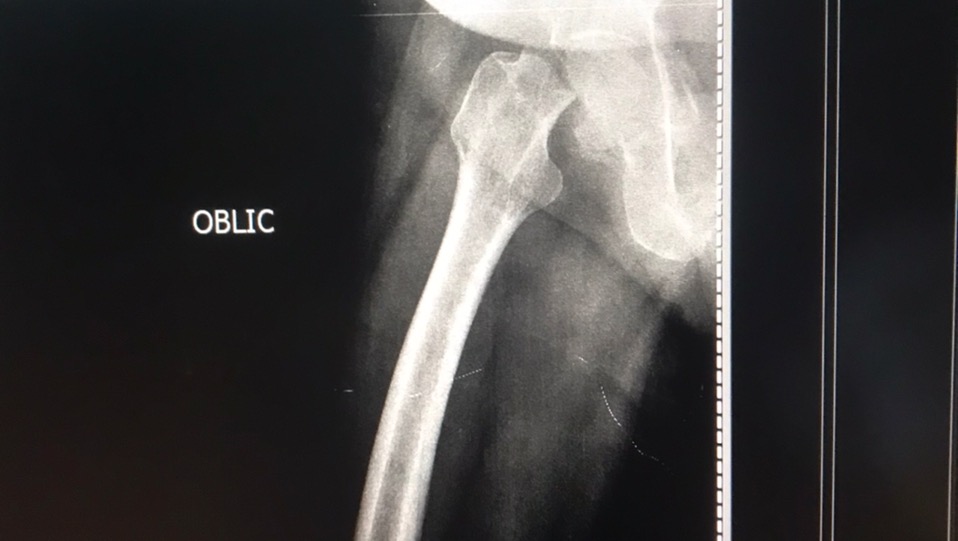

El motivo de esta campaña es para ayudar a la mamá de mi mejor amiga (Maria Alejandra Cáceres). Su mamá, la señora Ida Rincón, el 15 de diciembre, se presentó en la consulta de un traumatólogo en la ciudad de Maracaibo, por presentar un fuerte dolor en la entre pierna. Sorpresa para sus familiares cuando los resultados de los rayos X mostraron una fractura en la cabeza del fémur, y la única forma de solventar el problema es con una prótesis de cadera total derecha.